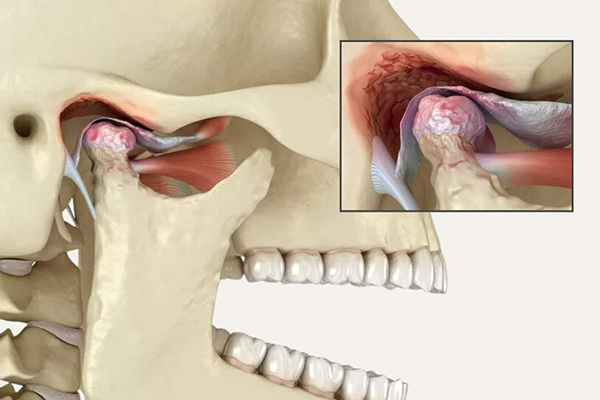

Temporomandibular Joint (TMJ) disorders can cause jaw pain, clicking sounds, limited movement, headaches, and difficulty eating. At Kamala Dental Super Speciality Hospital in Thiruvananthapuram, our team of dentists, led by Dr. Segin Chandran, an Oral and Maxillofacial Surgeon, provides personalized surgical and non-surgical TMJ treatments to restore function, comfort and proper jaw alignment.

- Arthritis or degenerative joint changes

- Surgical Correction: For complex or structural joint disorders, procedures such as arthroscopy, joint reconstruction, or open joint surgery are performed with precision using advanced digital planning protocols.

- Total joint replacement: A surgical solution to restore movement and function in fused or ankylosed jaws, using custom-designed artificial joints.